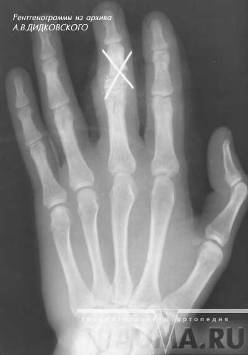

Рисунок 5 - Перелом основания средней фаланги 3 пальца кисти со смещением остеосинтез спицами.